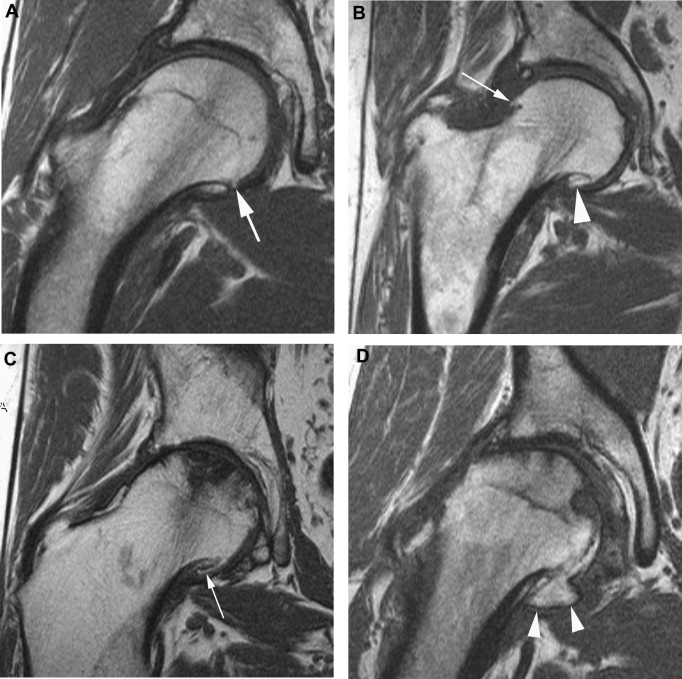

Hip Labral Tears are often associated with FAI but may also occur due to trauma or degenerative changes. Such tears compromise joint stability, often resulting in pain and restricted hip rotation.

Diagnostic Approach

Labral tears are most effectively diagnosed using MRI arthrogram, which provides detailed imaging of labral tissue and surrounding structures. This enables surgeons to accurately assess tear patterns and plan surgical repair.